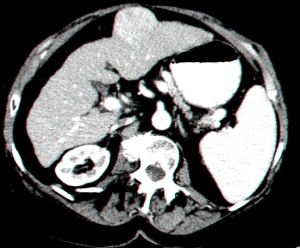

השיטות לאבחון גרורות בכבד הן: אולטראסאונד שבהכוונתו ניתן לבצע ניקור של הכבד ואבחנה של מהות הגוש. CT היא בדיקת הבחירה להדגמת גרורות בכבד ובהכוונתה ניתן לדגום את הגרורות (תצלום 37.10).

| תצלום 37.10: גרורות מרובות בכבד הנראות ב- CT (חץ). | |

|---|---|